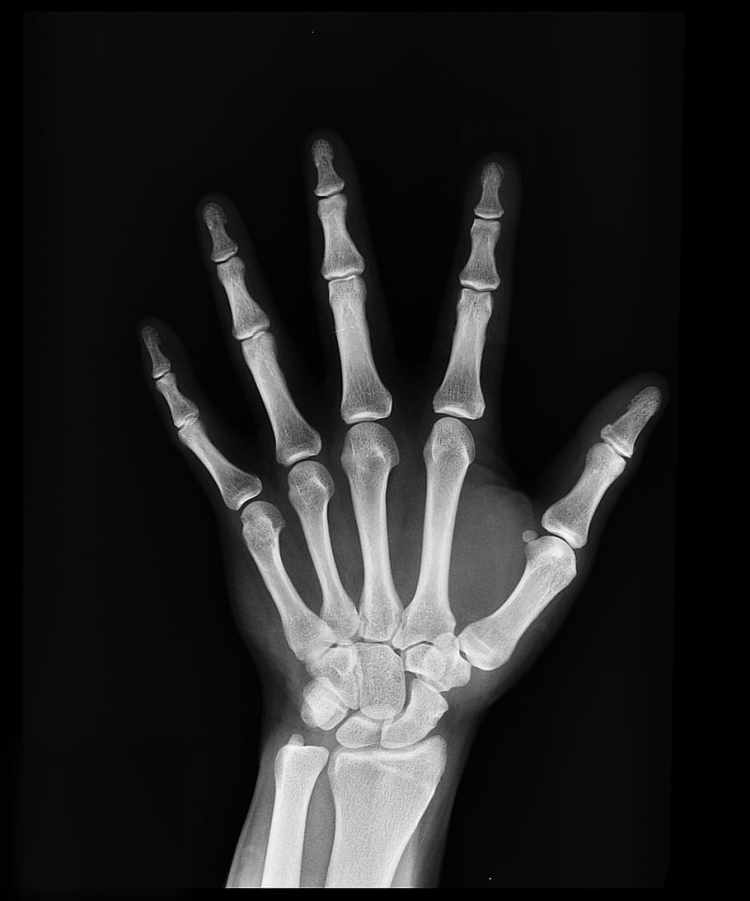

La magnitud de los riesgos derivados de bajas dosis de radiación es una de las cuestiones centrales en la protección radiológica. Es particularmente relevante cuando se discute la justificación y optimización de las exposiciones médicas de diagnóstico. Sin duda, los rayos X médicos pueden conferir beneficios sustanciales en el cuidado de la salud de los pacientes, no sin exponerlos a dosis efectivas que van desde unos pocos microsieverts hasta algunas decenas de milisieverts.